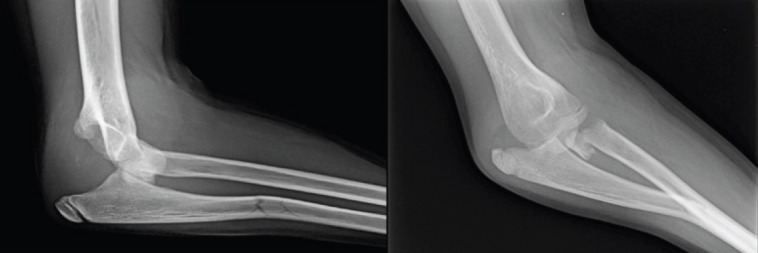

Introduction: Association of elbow dislocation, radial neck fracture (RNF), and ulnar shaft fracture has not been reported previously in the pediatric population.

Case report: This 11-year-old girl fell from her height. She presented a severely displaced RNF, a greenstick fracture of the proximal ulnar shaft, and a posterior elbow dislocation.

Conclusion: This article describes a very rare case, shows a possible treatment, and presents the follow-up with a final good result.